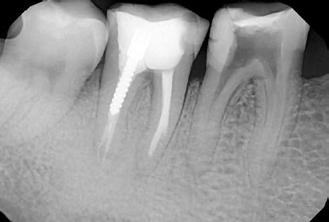

1. ábra: A 15-ös foggyökér meziális felszíne mellett látható radiolucens elváltozás, illetve a felvételen látható a korábban behelyezett gyökértömés, a parapulpális csap segítségével elhorgonyzott csonkfelépítés és a fogat borító cirkonkorona. –2. ábra: A saggitalis irányú CBCT-metszeten jól megfigyelhető az állcsontgerincet elérő radiolucens elváltozás. – 3. ábra: Az axiális irányú CBCT-metszeten egyértelműen látható a kezeletlen palatinális gyökércsatorna, valamint a radiolucens elváltozás mezio-disztális kiterjedése is jól megítélhető. – 4. ábra: A palatinális gyökércsatorna szelektív endodonciai kezelése során először gyógyszeres zárás került behelyezésre. – 5. ábra: A gyógyszeres zárás során alkalmazott kalcium-hidroxid alapú paszta a szulkuszon keresztül a szájüregbe extrudálódott. – 6. ábra: A gyökértömő anyag a középső és apikális gyökéri harmad határán lévő laterális csatornán keresztül a periapikális térbe extrudálódott. 7. ábra: A kezelések befejezését követően 4 évvel készült röntgenfelvételen jól látható a csontállomány gyógyulása és a fiziológiás gyökérhártyarés újbóli kialakulása. –8. ábra: A peroperatív CBCT-felvétel alapján készített koronális irányú metszeten jól látható a gyökércsúcs körül lévő periapikális felritkulás. – 9. ábra: A kezelések befejezése után 4 évvel készített CBCT-felvételen a gyulladásos lézió teljes megszűnése észlelhető.

A CBCT-készülékek endodonciai alkalmazásának talán az az egyik legnagyobb előnye, hogy így olyan anatómiai struktúrák is láthatóvá válnak, amelyeket egyébként nem tudnánk detektálni panoráma, cephalo, vagy periapicalis felvételek segítségével. Mivel a CBCT-felvételek kiértékelése számítógép segítségével történik, így a felvételek vizsgálata során lehetőségünk van az adott területet több nézőpontból és több síkban is megvizsgálni. 2015 októberében egy korábban a rendelőnkben kezelt 55 éves férfi páciens azzal a céllal kereste fel ismét a rendelőnket, hogy másodvéleményt kérjen egy jobb felső kvadránsban található fogával kapcsolatban. Egy másik rendelőben történő vizsgálat során a panaszos fog törését vélelmezték és a fog eltávolítását javasolták, illetve arról is beszámolt, hogy az elmúlt hét során ezen a területen egy puha duzzanat is kialakult. A klinikai vizsgálat során a jobb felső első és második kisőrlő között (14–15) egy fluktuáló duzzanatot észleltünk az áthajlásban. Az 15-ös fog mesialis oldalán 12 mm mély tasakot szondáztunk. A páciens által hozott periapicalis felvételen a 15-ös fog gyökércsúcsának mesialis részén egy nagy kiterjedésű radiolucens elváltozás volt észlelhető (1. ábra). A saggitális síkban vizsgált CBCT-felvételen (Carestream CS 9000, Carestream Dental) a lézió valódi kiterjedése is láthatóvá vált (2. ábra). A megelőző endodonciai kezelések során csupán a bukkális csatorna került detektálásra és gyökértöméssel való ellátásra. Az axiális irányú CBCT-szeleteken egyértelműen látható volt az ellátatlan palatinális gyökércsatorna (3. ábra)

Először kalcium-hidroxid alapú ideglenes gyógyszeres zárás került a palatinális csatornába (UltraCal XS, Ultradent Products; 4–5. ábra), amelyet 6 hét után a végleges gyökértömés elkészítése előtt eltávolítottunk. A gyökértömés elkészítése során meleg vertikális kondenzációs technikát alkalmaztunk. Radiológiai felvételen megfigyelhető volt, hogy a gyökértömő anyag egy laterális csatornán keresztül kis mennyiségben a periapicalis térbe extrudálódott (6. ábra). A 4 évvel később készített kontrollfelvételeken a lézió gyógyulása volt megfigyelhető (7–9. ábra). A vizsgálati eredmények és a kezelés kimenetele egyértelműen igazolta, hogy nem gyökérfraktúrával álltunk szemben, tehát a kezdeti diagnózis tévesnek bizonyult. Ez is azt erősíti, hogy korlátozott mennyiségben rendelkezésre álló adatok alapján nem lehet pontos diagnózist felállítani. Manapság szinte elengedhetetlen a CBCT-felvételek endodonciai beavatkozások során történő használata, feltéve, ha ezek elkészítése során az ALARA elv (as low as reasonably achievable) betartásra kerül.